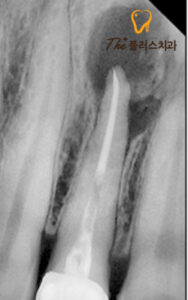

정밀한 상태를 파악하기 위해

x-ray를 촬영해 보았더니 이미 해당 치아 밑으로

염증이 심하게 진행되어 있었고,

인접한 치아로 염증이 이완되고 있는 상태였습니다.